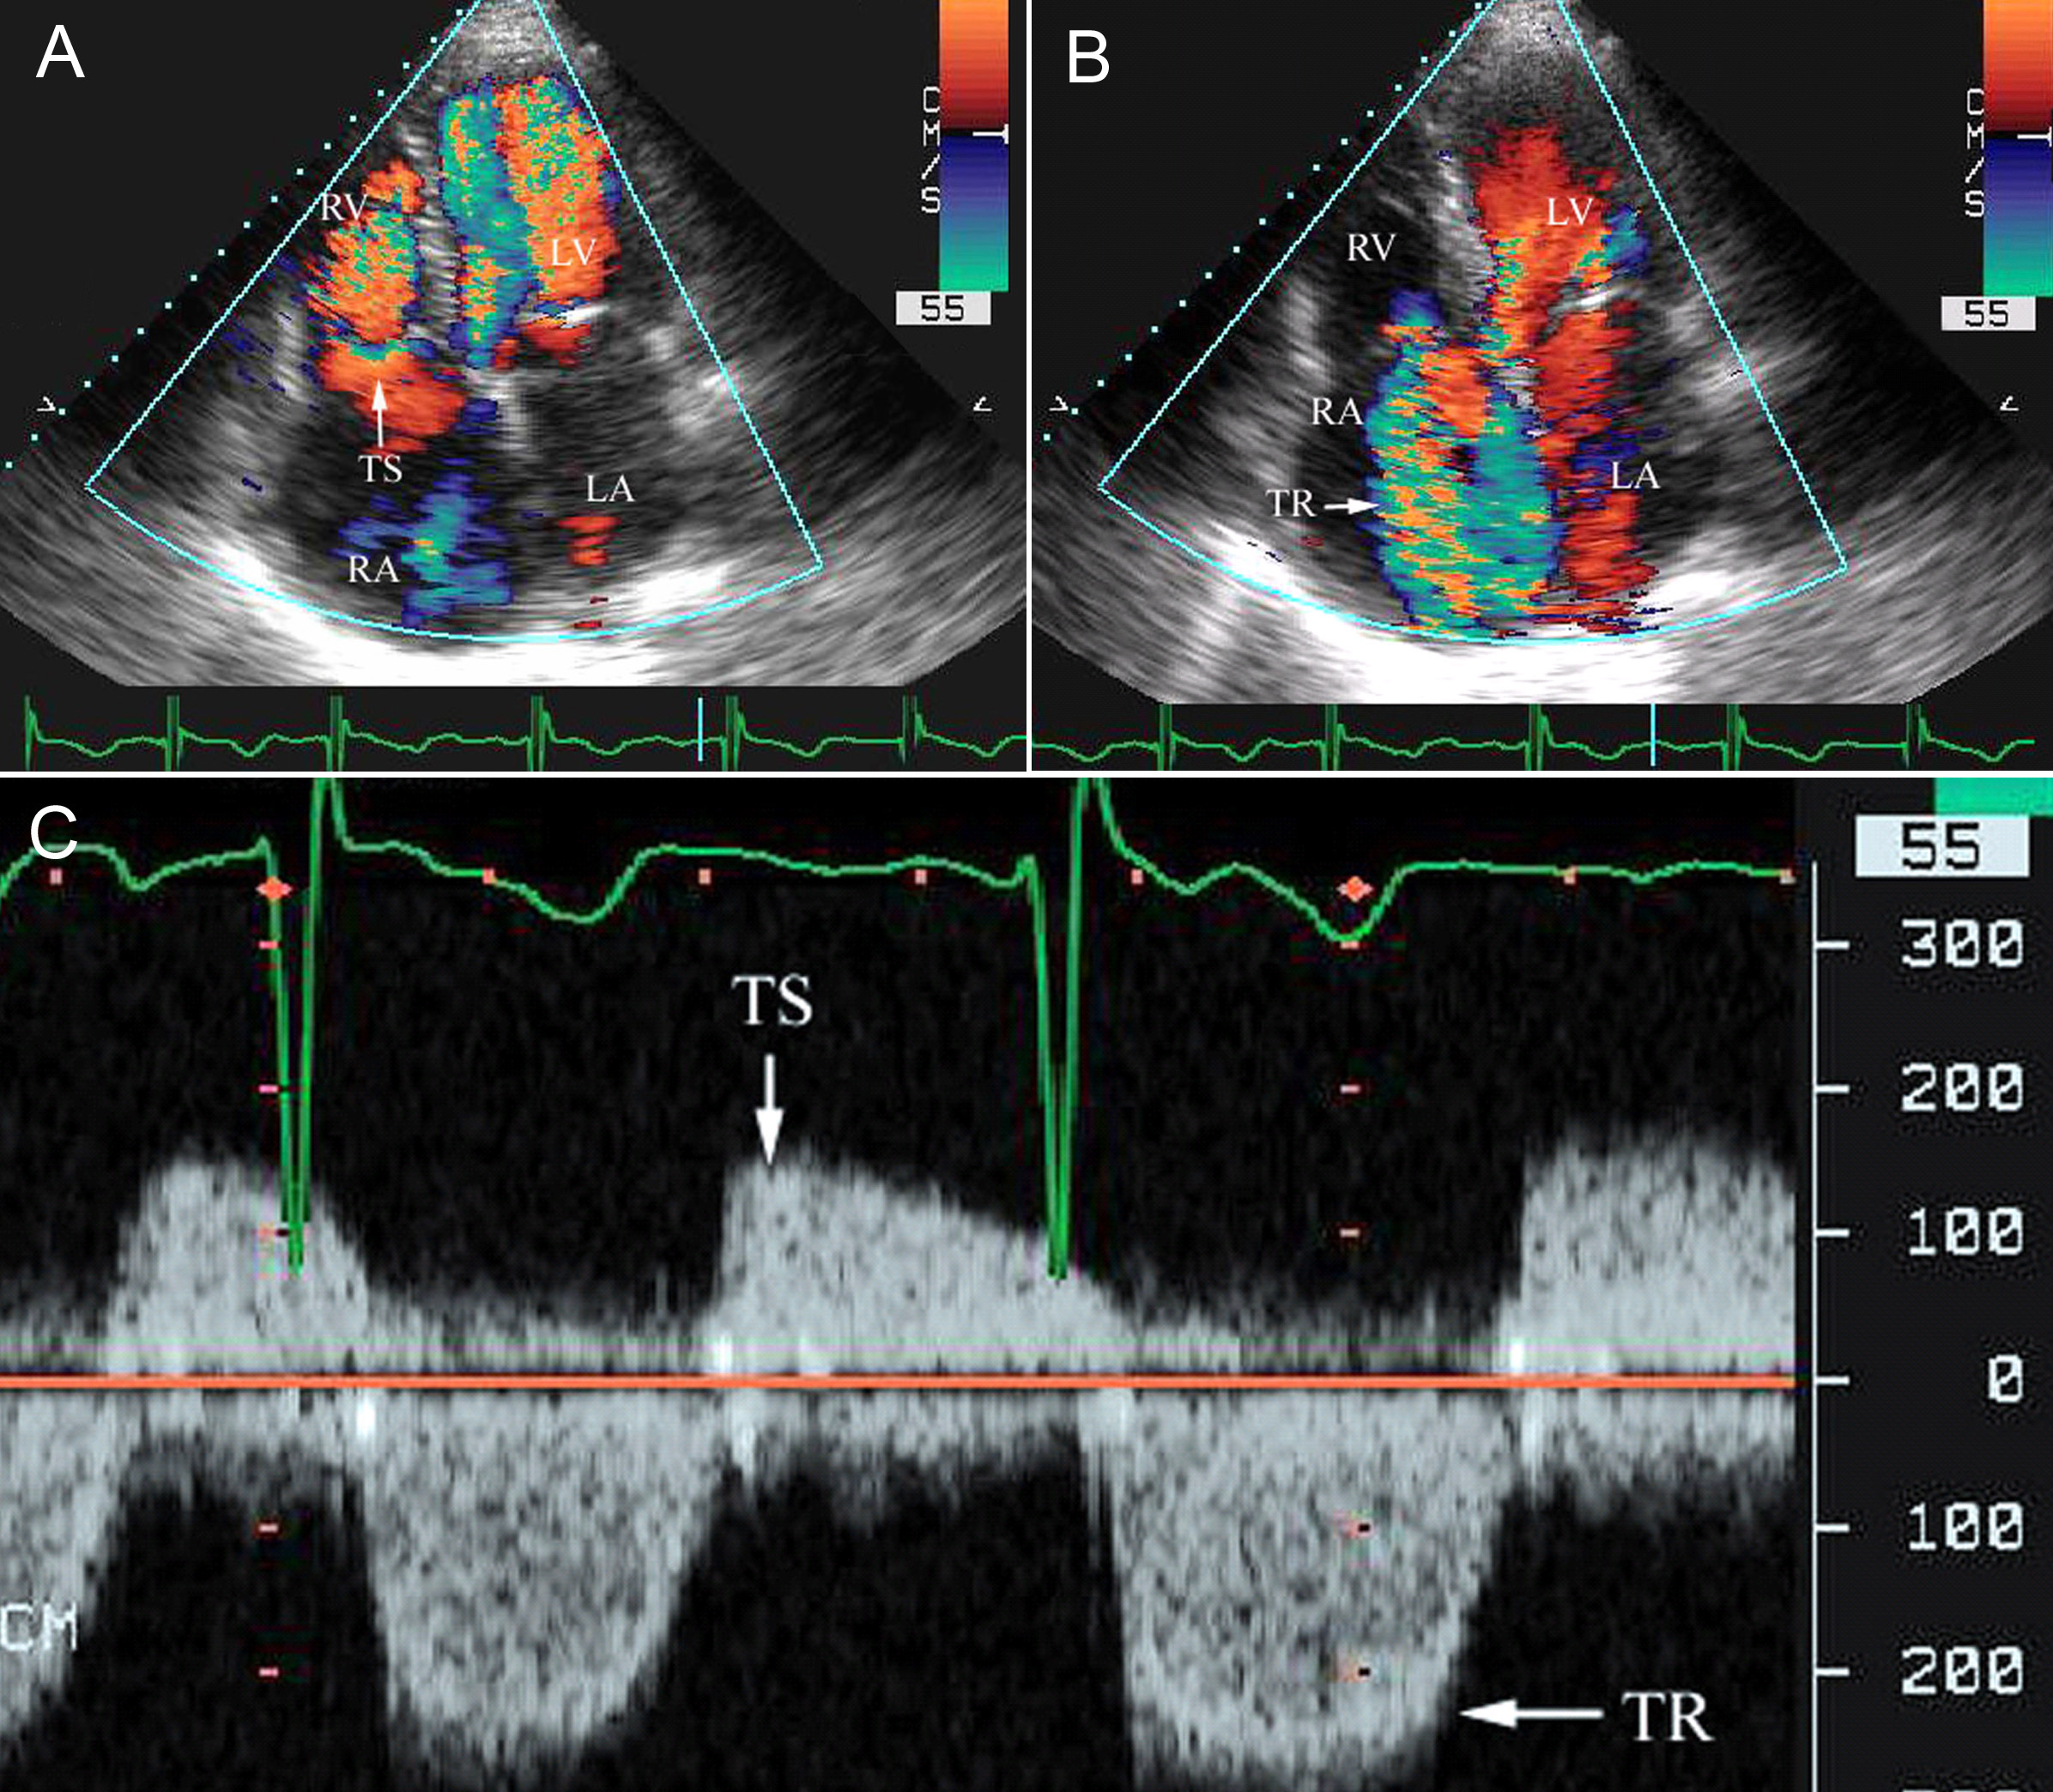

三尖瓣狭窄

三尖瓣狭窄,二尖瓣三尖瓣